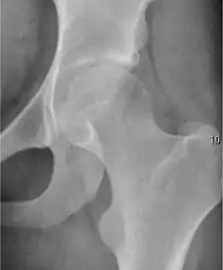

Projectional radiography ("X-ray") is the first imaging technique of choice in hip pain, not only in older people with suspected osteoarthritis but also in young people without any such suspicion. In this case plain radiography allows categorization as normal hip or dysplastic hip, or with impingement signs, pincer, cam, or a combination of both.[1]

Projectional radiography ("X-ray") is currently useful not only in older people in whom osteoarthritis of the hip is suspected but also in younger people without osteoarthritis, who are being evaluated for femoroacetabular impingement (FAI) or hip dysplasia.[1]

Plain radiography allows us to categorize the hip as normal or dysplastic or with impingement signs (pincer, cam, or a combination of both). Besides these, pathologic processes like osteoarthritis, inflammatory diseases, infection, or tumors can also be identified (Figure 1).[1]

- Osteoarthritis

In adults, one of the main indications for radiographs is the detection of osteoarthritic changes (Figure 1(e)). Nevertheless, radiographs usually detect advanced osteoarthritis that can be graded according to the Tönnis classifications. The grading system ranges from 0 to 3, where 0 shows no sign of osteoarthritis. Intermediate grade 1 shows mild sclerosis of the head and acetabulum, slight joint space narrowing, and marginal osteophyte lipping. Grade 2 presents with small cysts in the femoral head or acetabulum, moderate joint space narrowing, and moderate loss of sphericity of the femoral head. Grade 3 is the severest form of osteoarthritis, which manifests as severe narrowing of the joint space, large subchondral cyst with productive bone changes that may lead to deformity of the bone components of the joint, while secondary osteoarthritis due to calcium pyrophosphate deposition can be diagnosed when calcification of hyaline cartilage and fibrocartilage is detected.[1]

There are other pathological conditions that can affect the hip joint and radiographs help to make the appropriate diagnosis. Acute bacterial septic arthritis can be diagnosed by radiographs when a fast regional osteoporosis and destructive monoarticular process develops (Figure 1(f)). In case of tuberculous or brucella arthritis it is manifested as a slow progressive process, and diagnosis may be delayed.[1]